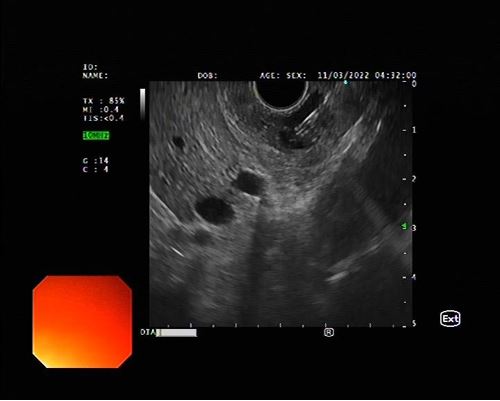

– Máy nội soi siêu âm hiện đại EU-ME 2 của Olympus

– Đầu dây nội soi có bộ phận phát sóng siêu âm khi đưa vào trong ống tiêu hóa cho phép quan sát, phát hiện tổn thương của các tạng sâu trong ổ bụng mà bình thường siêu âm qua thành bụng không thể thăm dò, phát hiện được.